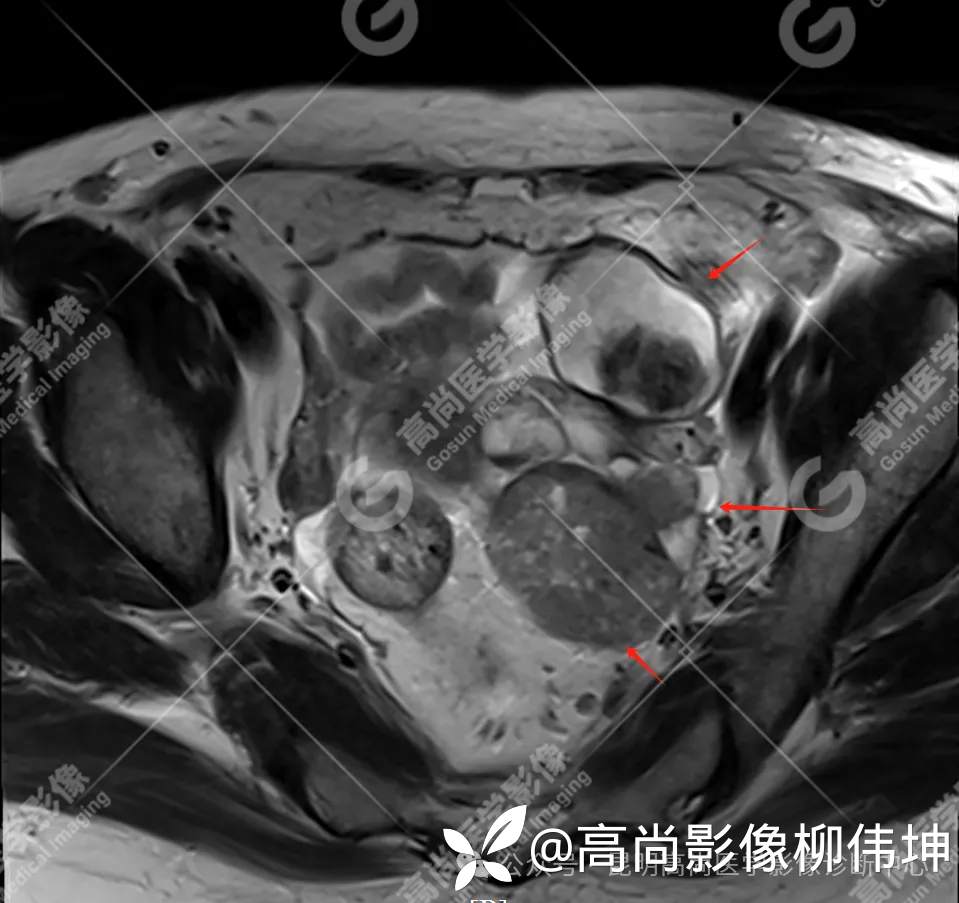

T2WI-tra

(2)MRI表现:通常双侧发生,体积巨大,呈外生性、囊实性、乳头状生长,其内见大量长T1长T2液性信号影及线性分隔,囊壁厚薄不均,可见壁结节及不同比例实性成分,呈T1等信号,T2略高信号。扩散受限,DWI呈高信号,ADC呈低信号。增强扫描实性成明显强化。另外,常可检出腹水、腹膜增厚、盆壁及盆腔脏器受累、淋巴结肿大等表现。